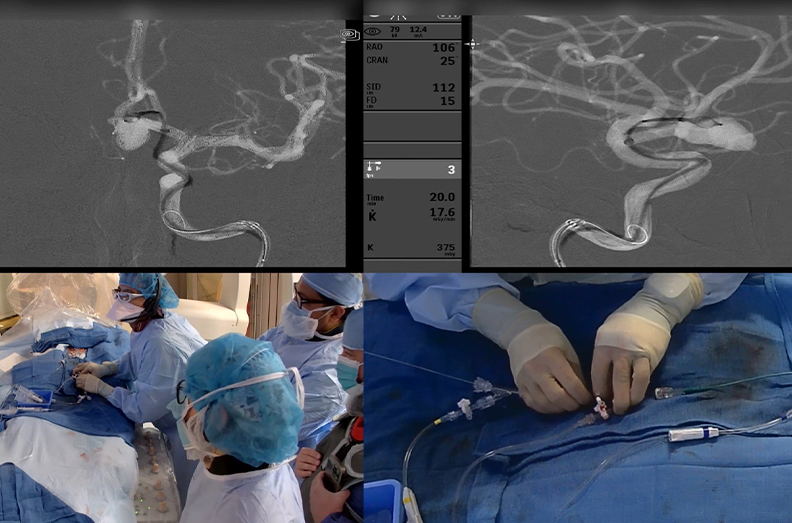

- Cerebral angiography: This minimally invasive test uses dye to enhance X-ray images. Your doctor inserts a thin tube (catheter) into a blood vessel in your groin or wrist and threads it to an artery in your neck. They release the dye while taking X-rays. If your doctor finds an aneurysm, they may treat it during the test by passing small tools through the tube.

- Brain aneurysm coiling and stenting: These minimally invasive techniques involve inserting a thin tube into an artery to reach the aneurysm. The neurosurgeon may then place coils of wire inside the aneurysm to cut off blood flow. Or they may put a metal mesh tube (stent) inside the blood vessel to provide stability.